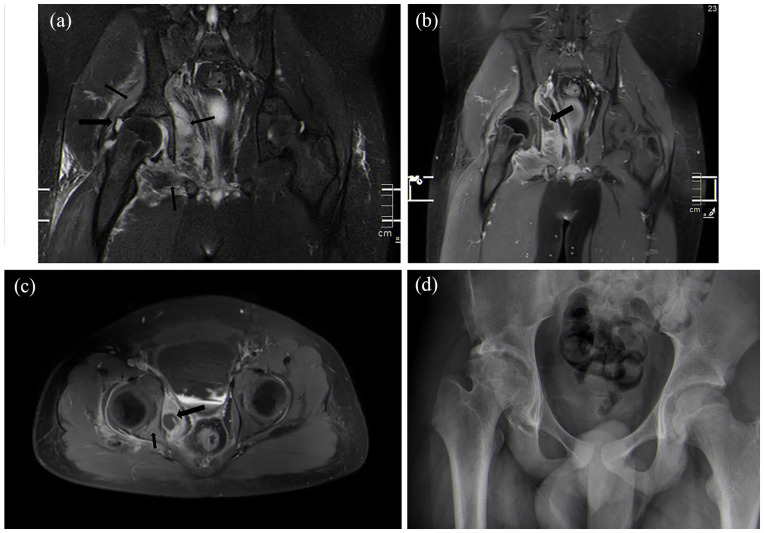

Results: Thirteen of 164 patients (7.9%) developed avascular necrosis. Avascular necrosis was noted in 9 of 101 patients who had anterior approach and 4 of 63 patients who underwent medial approach (p = 0.76). The average age for patients developing avascular necrosis was 10.0 years old versus 6.8 years old in patients who did not develop avascular necrosis (p = 0.01). The average follow-up was 3.3 years in patients with avascular necrosis versus 1.5 years for patients who did not develop avascular necrosis (p = 0.01).

Conclusion: Medial approach to the pediatric septic hip does not increase the rate of avascular necrosis compared to the anterior approach.